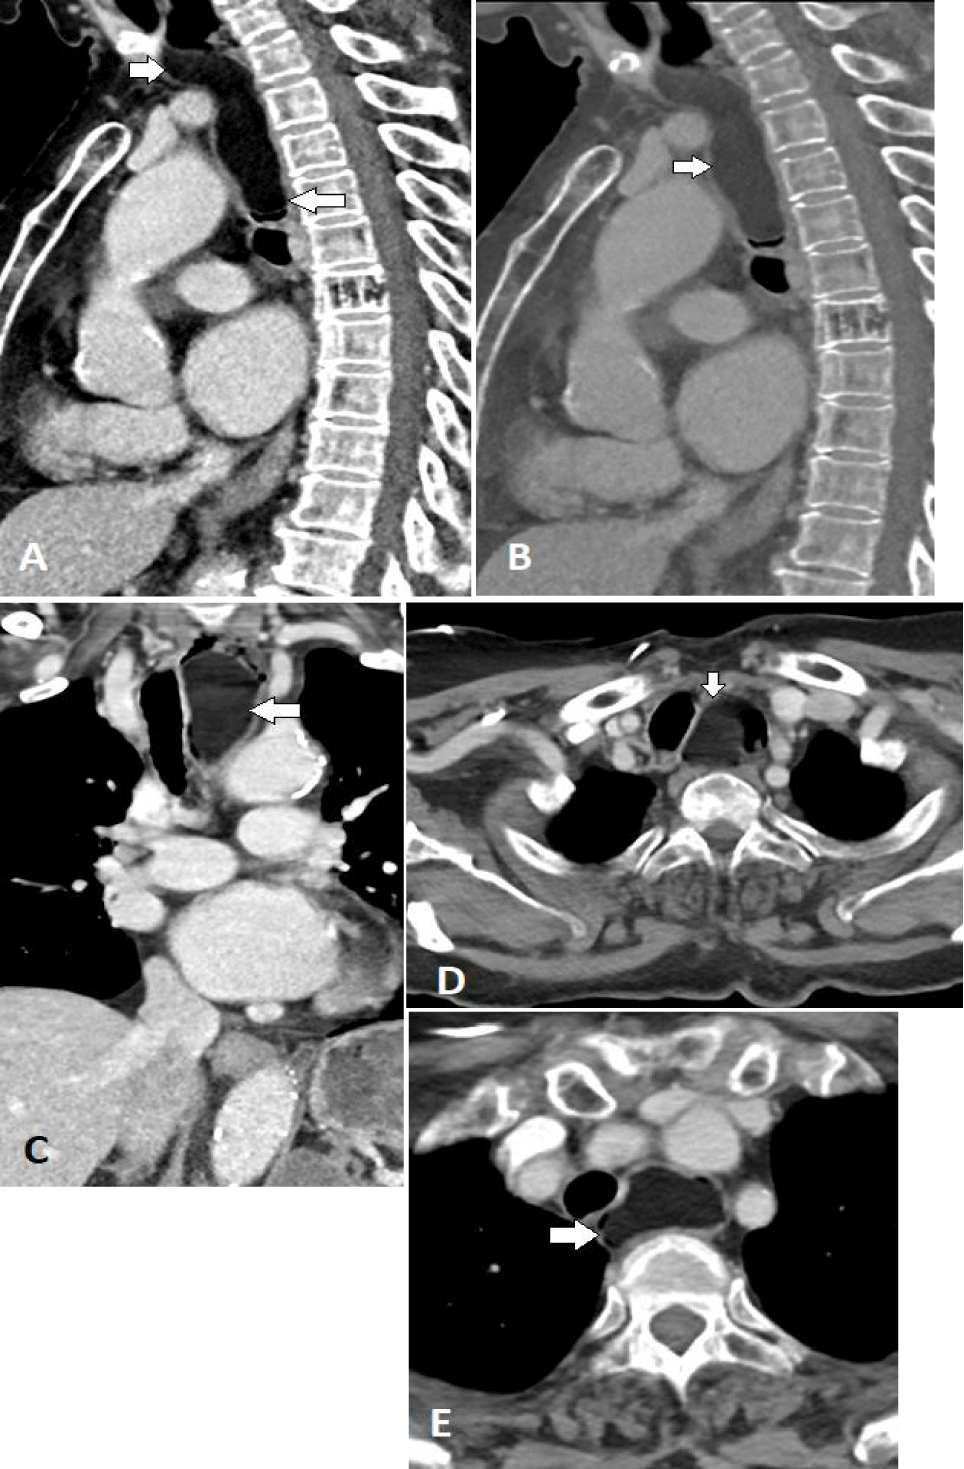

A chest X-ray (Figure1) revealed a soft tissue density in the middle mediastinal compartment, causing compression of the oesophageal column with smooth tapering. A further assessment by CT scan of the chest (Figure 2) identified a pedunculated, fat-density mass in the upper third of the oesophagus, resulting in obstruction and mild dilation of the proximal oesophagus, consistent with the lesion observed in the previous radiograph. No oesophageal thickening or abnormal enhancement was present, no soft tissue component and there was no enlargement of local lymph nodes.